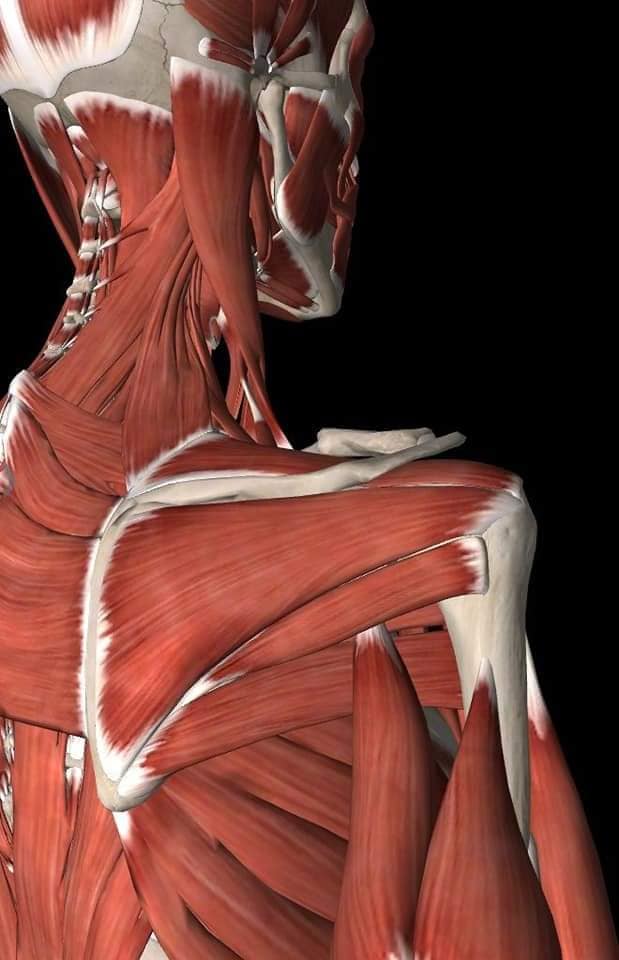

М'язова система людини є однією з основних систем організму, що відповідає за рухи, підтримання пози та стабільність. Вона складається з понад 600 м'язів, які можна класифікувати на скелетні, гладкі та серцеві м'язи. Скелетні м'язи, які є об'єктом нашого детального розгляду, дозволяють контролювати навколишній світ і виконувати різноманітні рухи. Особливу увагу в нашій статті буде приділено шейним і спинним м'язам, оскільки ці групи м'язів мають критичне значення для підтримання правильного постава та функціонування хребта.

Спинні м'язи

Спинні м'язи виконують функції підтримки хребта, а також дозволяють здійснювати рухи тулуба.

Поверхневі спинні м'язи

М'язи, що піднімають лопатку: Трапецієподібний м'яз: великий м'яз, що покриває верхню частину спини. Його функція - підтримка і рух лопаток, а також забезпечення стабільності хребта.

М'язи, що ведуть лопатку до хребта: Широкий м'яз спини: великий м'яз, що розташований в нижній частині спини. Він відповідає за рухи плечей і лопаток, а також за розширення верхньої частини тулуба.